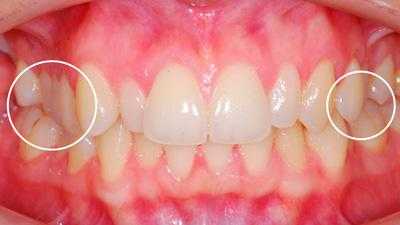

Определяющими внутриротовыми признаками дистального прикуса служат выдвижение вперед верхних фронтальных зубов; несмыкание верхних и нижних резцов с наличием между ними сагиттальной щели; нарушение взаимного расположения боковых зубов в переднезаднем направлении. В чистом виде дистальный прикус встречается редко; гораздо чаще он сочетается с аномалиями положения зубов, диастемой, тремами, глубоким, открытым или перекрестным прикусом, готическим нёбом.

Внутриротовые признаки

В полости рта дистальный прикус определяется по выступающим вперед верхним фронтальным зубам. В норме, при ортогнатическом прикусе, верхние резцы перекрывают нижние примерно на 1/3. При дистальной патологии между верхними и нижними резцами образуется расстояние — «саггитальная щель».

- I подкласс — верхние резцы направлены вперед, иногда немного вверх. Для этого вида дистальной окклюзии характерная саггитальная щель.